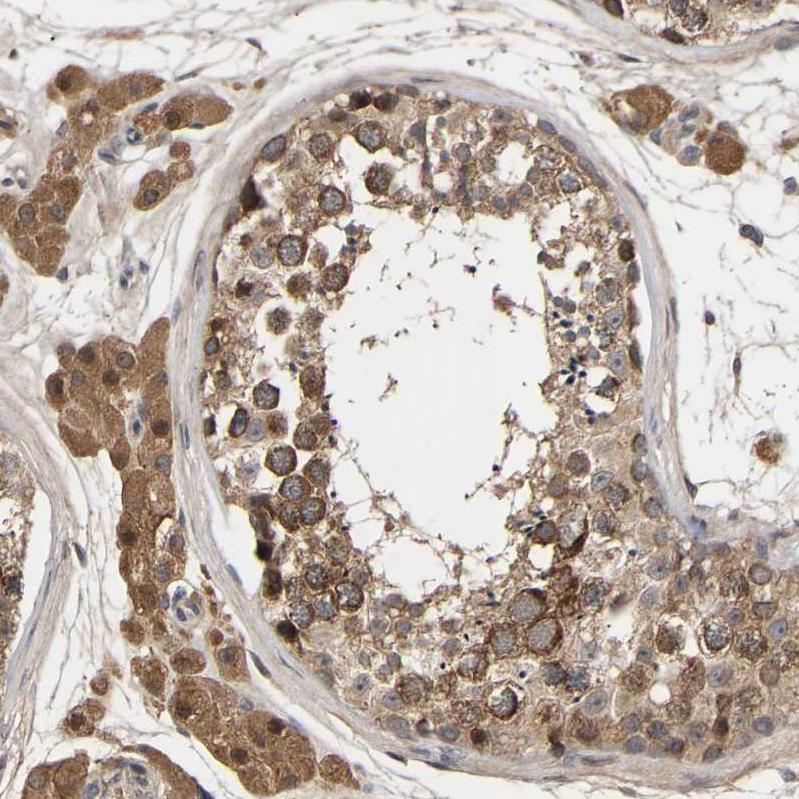

Immunohistochemical staining of human cerebral cortex, gastrointestinal, lymphoid tissues and testis using Anti-CCDC155 antibody HPA019940 (A) shows similar protein distribution across tissues to independent antibody HPA019937 (B).